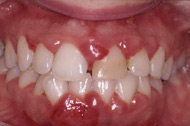

正常牙周組織